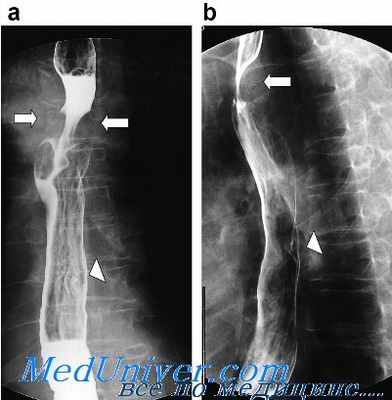

Перед началом исследования выполняется обзорная рентгеноскопия грудной клетки. Затем больному дают выпить небольшой глоток бариевого контраста. Рентгенолог на мониторе рентгеновской установки прослеживает акт глотания и скорость продвижения бария в желудок. После того как больной выпивает всю бариевую взвесь, выполняют снимки в прямой, боковых, косой проекциях. Рентгенография пищевода проводится в положении стоя, иногда – лежа.

При описании снимков пищевода рентгенолог указывает характеристики акта глотания, состояние стенок пищевода; наличие стенозов и выпячиваний, свищей и язв, опухолевых деформаций; рельеф слизистой в патологически измененной зоне. По результатам рентгенографии пищевода с барием могут быть выявлены следующие патологические изменения, характерные для определенных заболеваний:

Рентгенологическое исследование пищевода начинают с рентгеноскопии и, если это необходимо, заканчивают рентгенографией. Как правило, обследование пищевода проводят с помощью контрастирования его стенок. Для этого применяют либо жидкую, либо густую бариевую смесь. Особенно часто прибегают к контрастированию при диагностике мелких инородных тел в пищеводе. Для этого весьма удобен метод Ивановой-Подобед. Больному дают выпить жидкий барий и сразу вслед за этим глоток воды. Со стенок пищевода барий смывается, но остается, как правило, на инородном теле.

При рентгенологическом исследовании обращают внимание на форму, положение, размеры, контуры, рельеф и толщину слизистой оболочки, тонус и функцию пищевода.

При воспалительных процессах в мягких тканях их толщина увеличивается и пищевод как бы отделяется либо от позвоночника, либо от трахеи. При травматических повреждениях слизистой оболочки пищевода на боковых рентгенограммах шеи отмечается характерное просветление с четкими ровными контурами — скопление воздуха (симптом «воздушной стрелки»), что связано с воспалительным отеком травмированной слизистой оболочки пищевода, сужением его просвета и задержкой воздуха, выходящего из желудка.